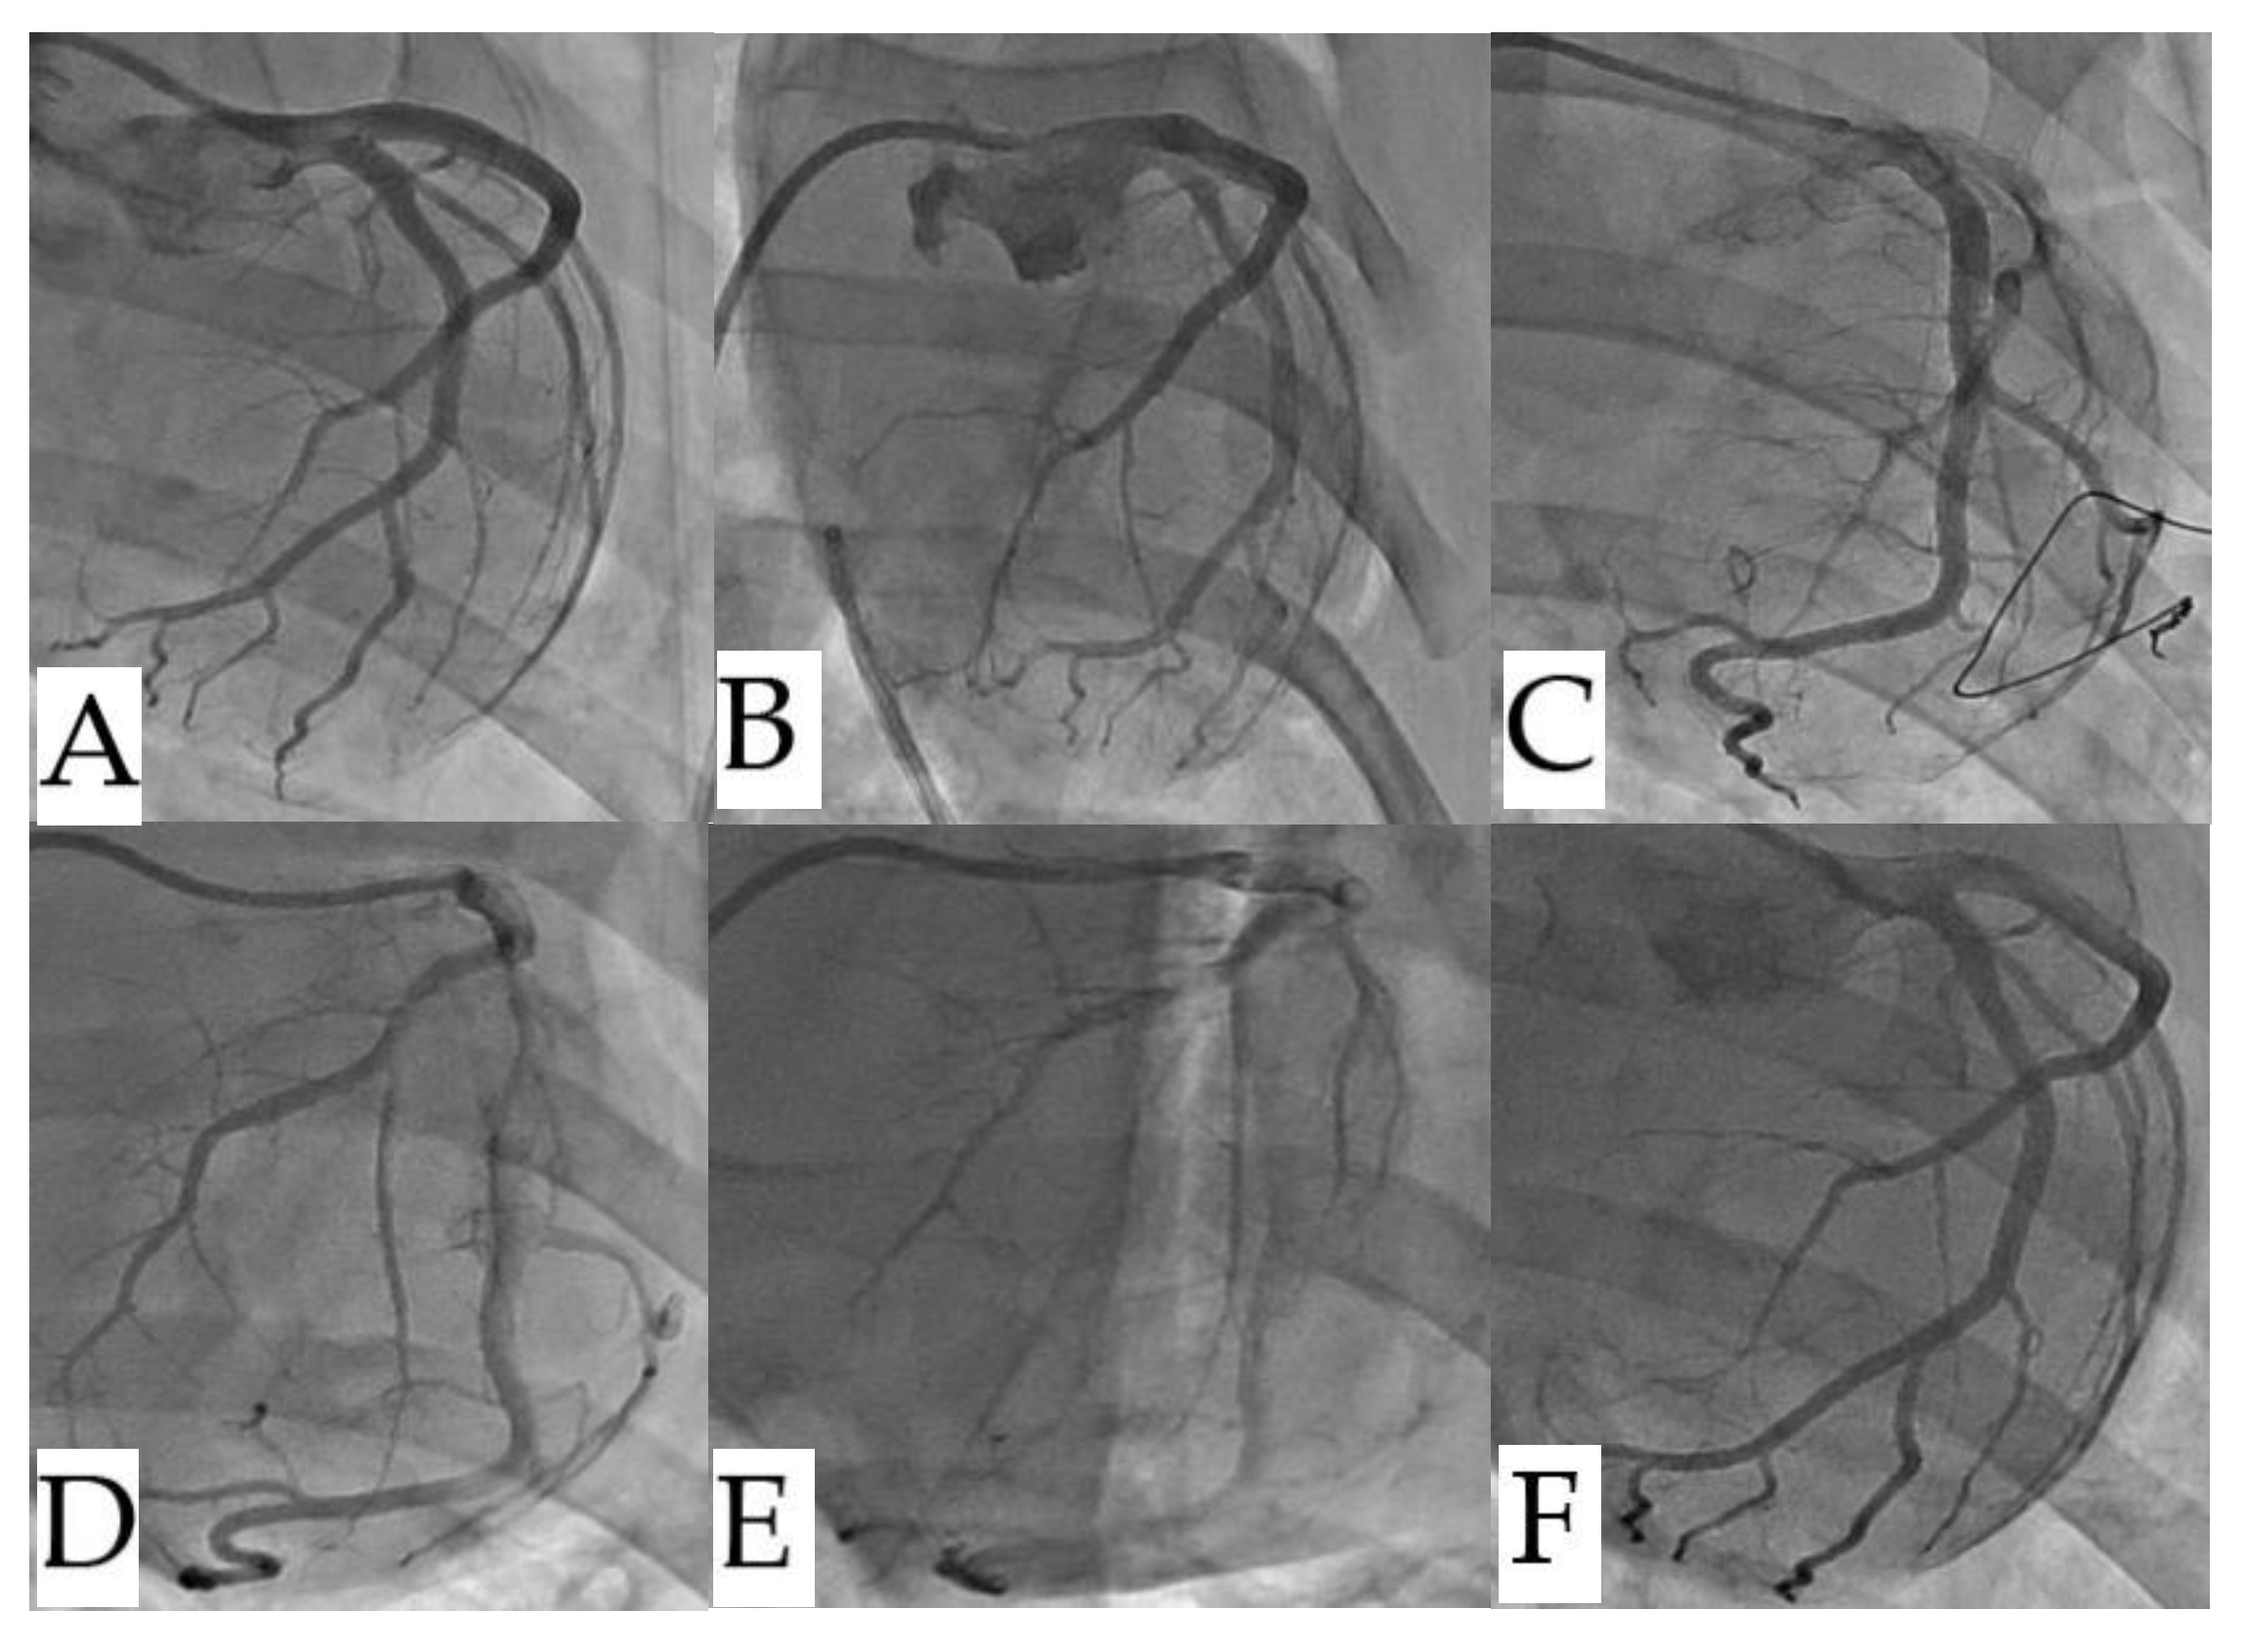

Coronary arteriography revealed that septal branch vascularization was not significantly impacted neither RFA nor nsPFA (

Figure 5).

Figure 5.

Comparison of coronary angiography before and after ablation. (Top row: RF ablation animal; Bottom row: nsPEF ablation animal). (A,C).before ablation, (B,D). immediately after ablation, and (E,F). seven days after ablation. There were no significant abnormalities found on left coronary septal branch angiography in either group. nsPEF, nanosecond pulsed electric field; RF, radiofrequency.